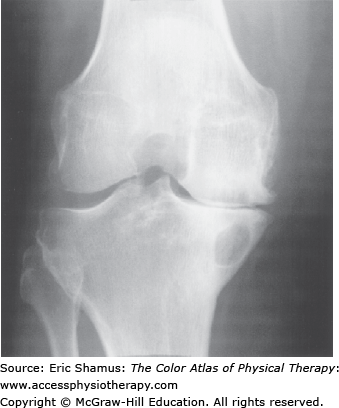

Patient is a 70-year-old male that presents with bilateral knee pain. Patient states the pain in both of his knees has been progressively getting worse over the last 10 years. About 5 years ago, he had bilateral knee arthroscopies to clean out the joints. Last year, he had a Synvisc injection with some relief. The patient has limited knee ROM with bilateral genu varum. He states that if he is on his feet for any period of time he needs to sit down. The patient has morning stiffness. If he rides his stationary bike for a few minutes, the knee pain subsides for a little. He finds pool exercises are helping. The x-ray shows bilateral decreased joint space. Which of the following activities would be the most helpful for this patient?